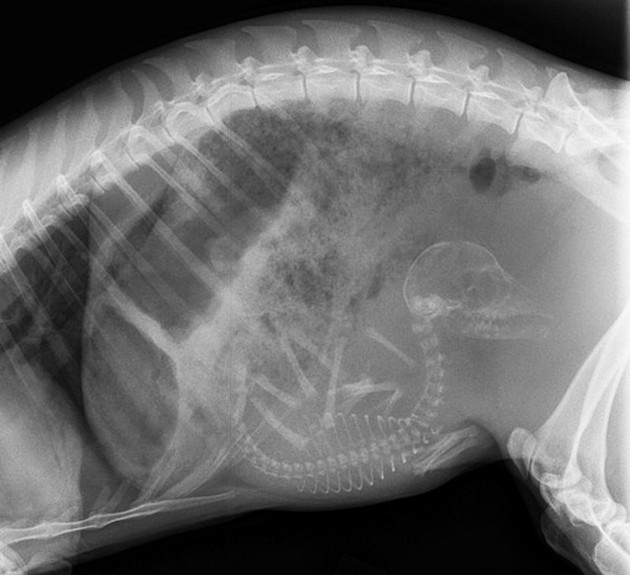

Radostné očakávanie môže u rôznych zvieracích druhov vyzerať všelijako. Fotky, ktoré vám dnes ukážeme sú raritné a rozhodne zaujímavé. Predsa len, videli ste už niekedy tehotné zvieratá cez röntgenové snímky?

Niektoré z nich rodia živé mláďatá, iné zasa kladú vajíčka. Zrod nového života vo zvieracej ríši je každopádne fascinujúci. A ako vyzerajú tehotné zvieratká sa môžete pozrieť na nasledujúcich “lekárskych” snímkoch.

Mačka